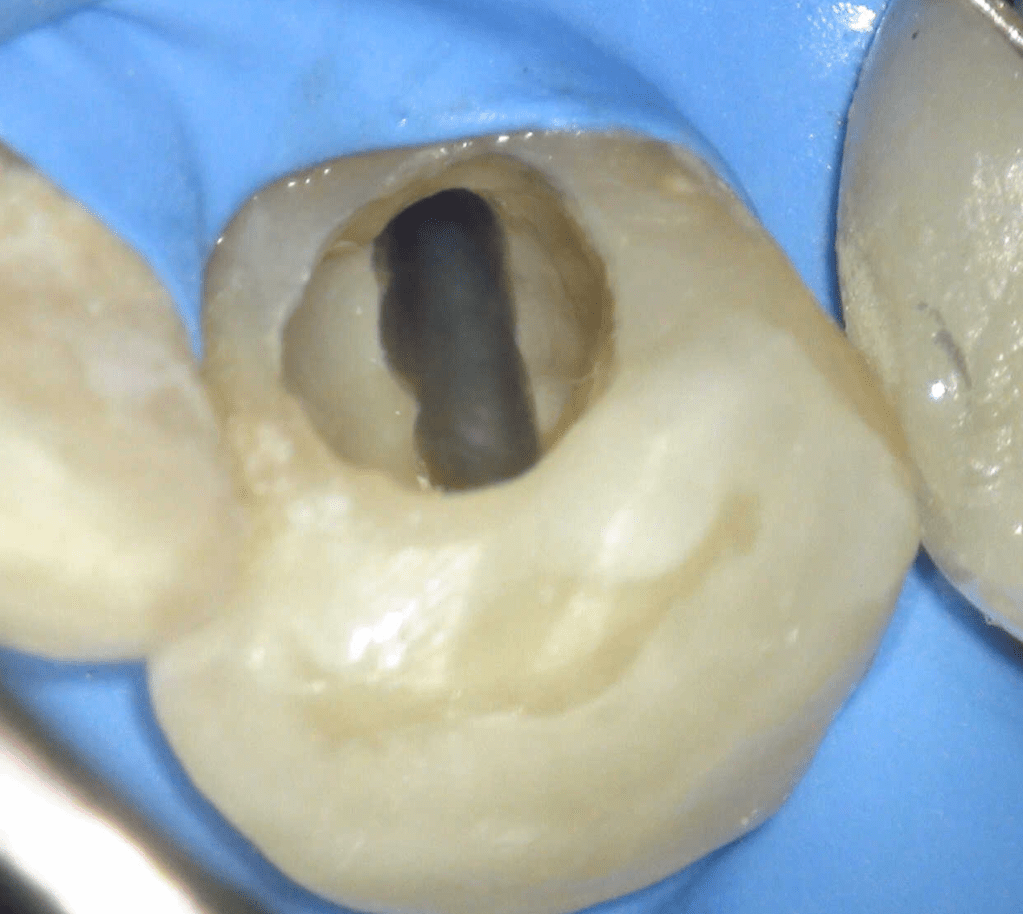

Reco pared vesticular